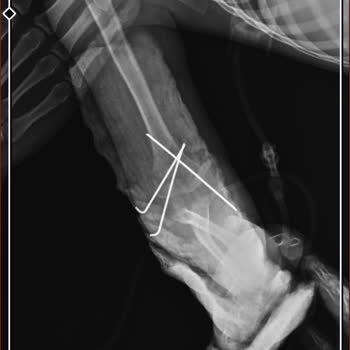

Baltalimanı Kemik Hastanesi Ortopedi bölümünde annemin yaşadığı mağduriyeti paylaşmak istiyorum. Annemin eli kırıldığı için 24 Nisan Cuma günü saat 16.00 civarında acil servise başvurduk, acilde ilk müdahale yapıldı ve ameliyat olması gerektiği söylendi. Bunun üzerine 27 Nisan Pazartesi günü tekrar ...